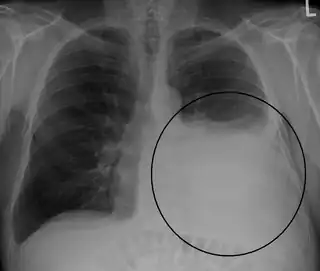

Radiografía de tórax que muestra un derrame pleural en el pulmón izquierdo (señalado con un círculo) | ||

El derrame se hace visible en la radiografía cuando es mayor de 75 ml, puede aparecer libre o loculado. En caso de que existan dudas, es recomendable la realización de una radiografía en decúbito lateral del lado afecto. El derrame pleural puede presentar imágenes radiológicas atípicas como:

- La imagen de la radiografía de tórax en el derrame pleural es usualmente característica a 200 ml de líquido pleural (LP) producen borramiento de los ángulos cardiofrénico y costodiafragmático. 50 a 75 ml de LP producen borramiento del ángulo costodiafragmático posterior en la radiografía lateral, observándose el denominado “signo del menisco”. La sensibilidad de la radiografía de tórax para detectar DP es 24-100% con especificidad 85-100% y la sensibilidad para detección del DP por utrasonido es 93% con especificidad 96%.